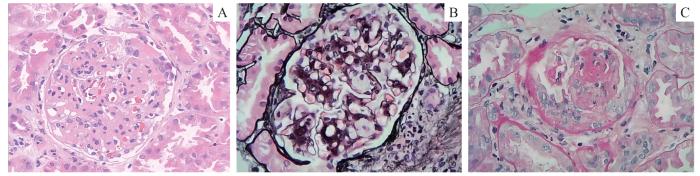

排除禁忌证后于2023年3月15日行超声引导下肾穿刺活检术,病理结果如下。① 光学显微镜:肾皮质及髓质共见15个肾小球,其中3个肾小球球性硬化,1个肾小球节段性硬化。其余肾小球系膜细胞和基质中-重度增生,呈结节状改变,以系膜基质增生更为明显;少数肾小球见节段性内皮细胞空泡变性,部分毛细血管腔狭窄,基底膜增厚,可见节段性系膜插入及双轨形成,但未见钉突样结构,上皮下、内皮下未见嗜复红蛋白沉积,可见1个小细胞性新月体形成;少数肾小球球囊周可见纤维化。肾小管上皮颗粒及空泡变性,可见个别蛋白及颗粒管型,多灶状萎缩(萎缩面积约35%),肾间质局灶水肿,多灶状炎症细胞浸润伴纤维化,细动脉管壁可见节段性玻璃样变,小动脉管壁增厚,管腔狭窄(图1)。② 免疫荧光染色:IgG(+++),为IgG1亚型;IgM(+);IgA(-);C3(+),沿肾小球系膜区呈颗粒样沉积;补体C1q(-);纤维蛋白原(fibrinogen,Fib)(-);白蛋白(albumin,Alb)(-);kappa(+);lambda(+);IgG沿肾小球毛细血管襻呈线状沉积,尚可见部分远端小管基底膜阳性(图2)。③ 电子显微镜:肾小球基底膜节段性增厚,足突弥漫融合,系膜细胞和基质增生明显,个别系膜区可见少量低密度电子致密物沉积(图3)。病理诊断:肾小球膜增生病变伴IgG线样阳性,符合非典型抗GBM肾炎。

图1

光学显微镜下观察肾脏组织(×400)

Note: A/B. Hematoxylin-eosin (H-E) staining (A) and periodic acid-silver methenamine (PASM) staining (B) show mesangial cells and stroma with moderate to severe hyperplasia, thickening of the basement membrane, segmental mesangial insertion, and “double track sign” formation. C. Periodic acid schiff (PAS) staining show microcytic crescent formation.

Fig 1

Observation of renal tissue under an optical microscope (×400)